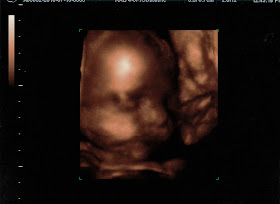

Emma Grace!!

Still a GIRL!

She looks JUST like Reese!

"High Kick" (that's her leg going straight up above her head!)

Knee in her face

Cheeks!

Mouth Open (she was sticking her tongue out!)

Holding her foot above her head!